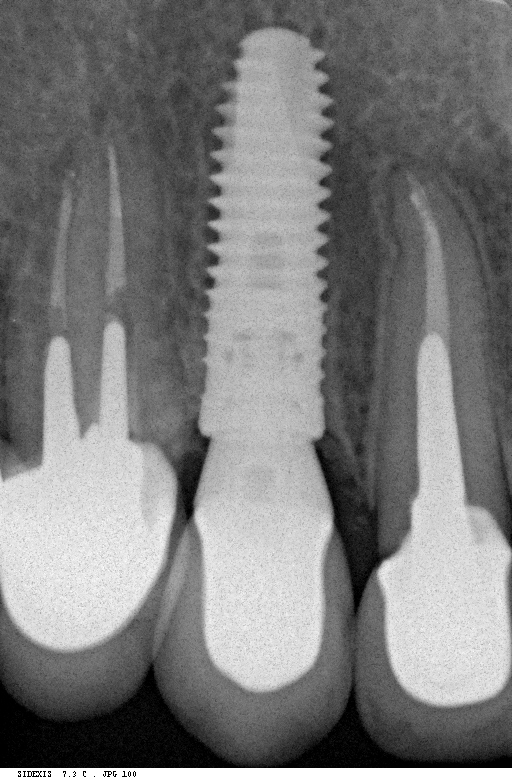

Рекомендации по установке имплантов. Для всех. Часть II.